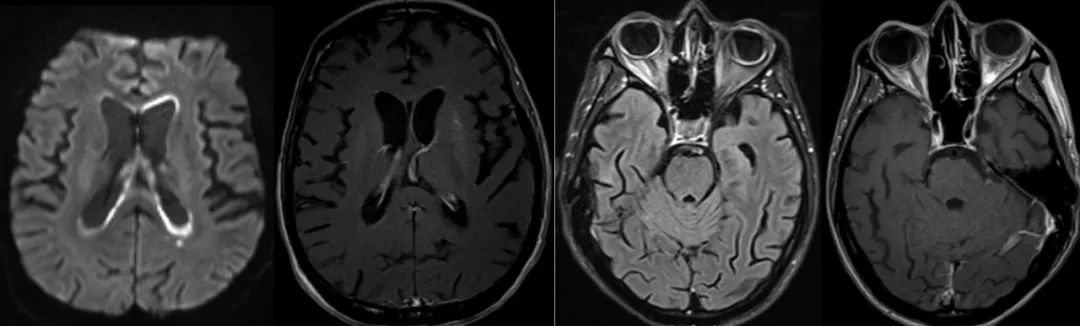

33岁男性,携带艾滋病毒,进行性加重的嗜睡、腹泻、腹痛和失明。

轴向DWI 显示侧脑室室管膜表面弥散受限(A)。相应的T1WI有轻微增强(B)。FLAIR (C)及T1WI 增强扫描(D)显示两侧葡萄膜增厚,右侧视网膜脱离。

成人机会性巨细胞病毒脑室脑炎的影像学表现是非特异性的。巨细胞病毒性视网膜炎和胃肠道受累是巨细胞病毒性感染的常见形式,但在所有巨细胞病毒性感染患者中,神经系统表现仅占不到1%。临床表现为:定向障碍、淡漠、退缩、颅神经病和眼球震颤。脑室脑炎是CMV感染中最常见的中枢神经系统受累形式,其特征是脑室内表面的室管膜炎。CMV引起的视网膜炎发生在大约三分之一没有接受HAART治疗的艾滋病患者中,并占与艾滋病毒感染相关的失明病例的90%以上。主要诊断特征:沿室管膜表面弥散受限伴/不伴造影增强。脉络膜视网膜炎表现为葡萄膜增强、视网膜脱离和视网膜钙化。巨细胞病毒引起的视网膜炎最常见于单眼,并进展到累及对侧眼。要与淋巴瘤和化脓性脑室炎相互鉴别。